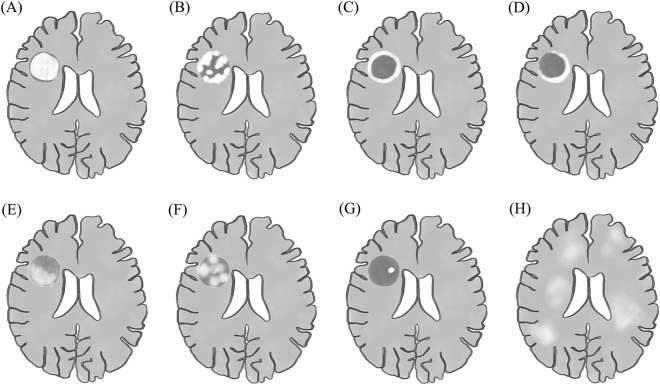

Brain MRI and computer tomography (CT) scans underwent comprehensive evaluation in collaboration with neuroradiologists. We documented the duration from the onset of symptoms to the scan. Complete radiological findings were gathered, encompassing lesion number, location, size, gadolinium enhancement pattern (homogeneous, heterogeneous, closed ring, open ring, patchy, or nodular, as depicted in Fig. 1), presence of restricted diffusion on diffusion-weighted imaging (DWI), the extent of perilesional edema (mild [< 1 cm from the lesion], moderate [1 to 3 cm from the lesion], or marked [> 3 cm from the lesion])24, and mass effect (mild [sulcal effacement], moderate [< 1 cm subfalcine or uncal herniation], or marked [> 1 cm subfalcine or uncal herniation])24. Furthermore, we noted the presence of established typical TDL features, including the T2W hypointense rim (a noticeable, complete, thin border of T2W hypointensity contrasting with the hyperintense regions of the lesion's core and the surrounding edema) and the central vein sign (a hypointense thin line or small dot visible in at least two planes, centrally situated within the lesion, seen on susceptibility- or T2*-weighted imaging).

Figure 1.

illustrates typical gadolinium-enhancing patterns of tumefactive demyelinating lesions (TDL), including (A) homogenous (dense and uniform enhancement across the entire lesion) (B) heterogenous (inconsistent and complicated pattern and arrangement of enhancement) (C) closed ring (a complete circular enhancing border) and (D) open ring (an incomplete enhancing border, with the open portion extending into the gray matter). In selected TDLs, the heterogenous pattern could be further specified as (E) patchy (irregular and discontinuous areas of enhancement within a specific lesion) (F) nodular (clearly delineated areas of enhancement, each measuring > 2 mm, within regions that do not exhibit enhancement) (G) punctate (clearly delineated areas of enhancement, each measuring < 2 mm, within regions that do not exhibit enhancement) or (H) cotton-ball (an appearance of small, round, and clustered areas of enhancement).